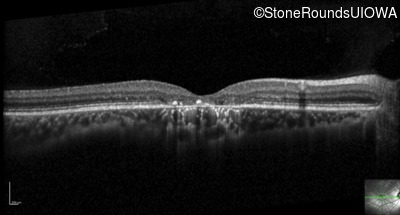

Optical Coherence Tomography - Left - 20/25 +2

Exemplar / OCT Stack